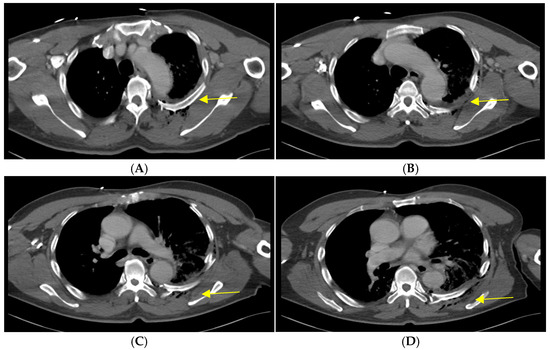

Due to the significant pulmonary contusion and dyspnea, the patient’s oxygen saturation dropped below 90% after WBCT was taken, and he was intubated and initially placed on ventilatory support. A thoracic trauma surgeon was consulted due to the radiologic flail chest, resultant respiratory compromise, and displaced posterior rib segments threatening the patient’s descending aorta. Early surgical stabilization was scheduled. The following day, rib CT was performed for surgical planning (Figure 2), and the patient was taken to the operating room for surgical stabilization of the rib fractures.

Figure 4. Axial view images of the post-operative rib CT showing costovertebral plating. The previously displaced 6th rib fragment (C) threatening the aorta is now aligned along with other flail segments (4th–7th, AD).